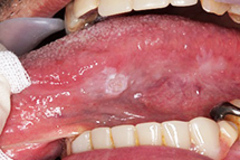

舌乳頭腫は、ウイルス性の良性腫瘍で、舌の表面に小さな隆起が形成されます。これらは通常無痛であり、自然に治癒することもありますが、外観上の問題が気になる場合は、医療機関での治療が考慮されます。

舌癌

舌癌は、舌に発生する最も一般的な悪性腫瘍で、特に扁平上皮癌が多いです。リスク因子としては、喫煙や飲酒、HPV感染が挙げられます。初期症状は軽微ですが、進行すると潰瘍が形成され、周囲の組織に浸潤することがあります。早期発見が重要で、定期的な口腔内のチェックが推奨されます。